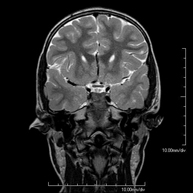

- Neuroradiology

- Brain MRI (cranial)

This non-invasive diagnostic procedure uses an electromagnetic field and radio waves (from a transmitter and receiver) to acquire high-definition anatomical images of the brain. It is a radiation-free procedure. Indicated for: vascular problems, memory loss, epilepsy, headache, malformations, suspected tumour, meningitis.